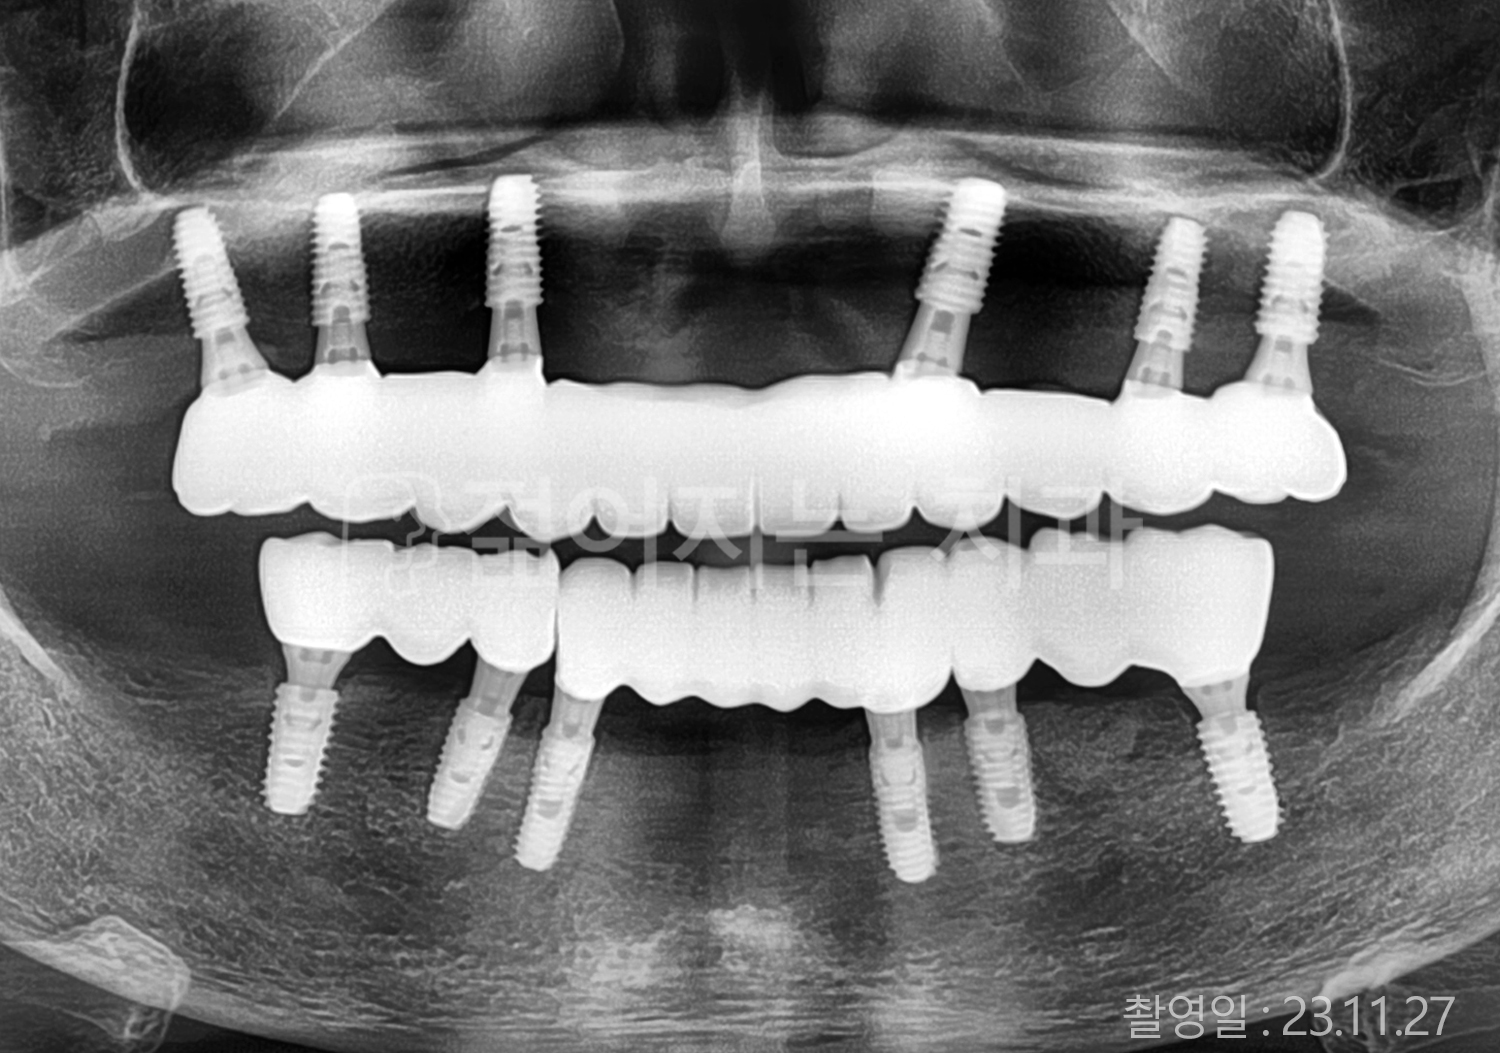

• 60대 전체치아 10개 이상 임플란트